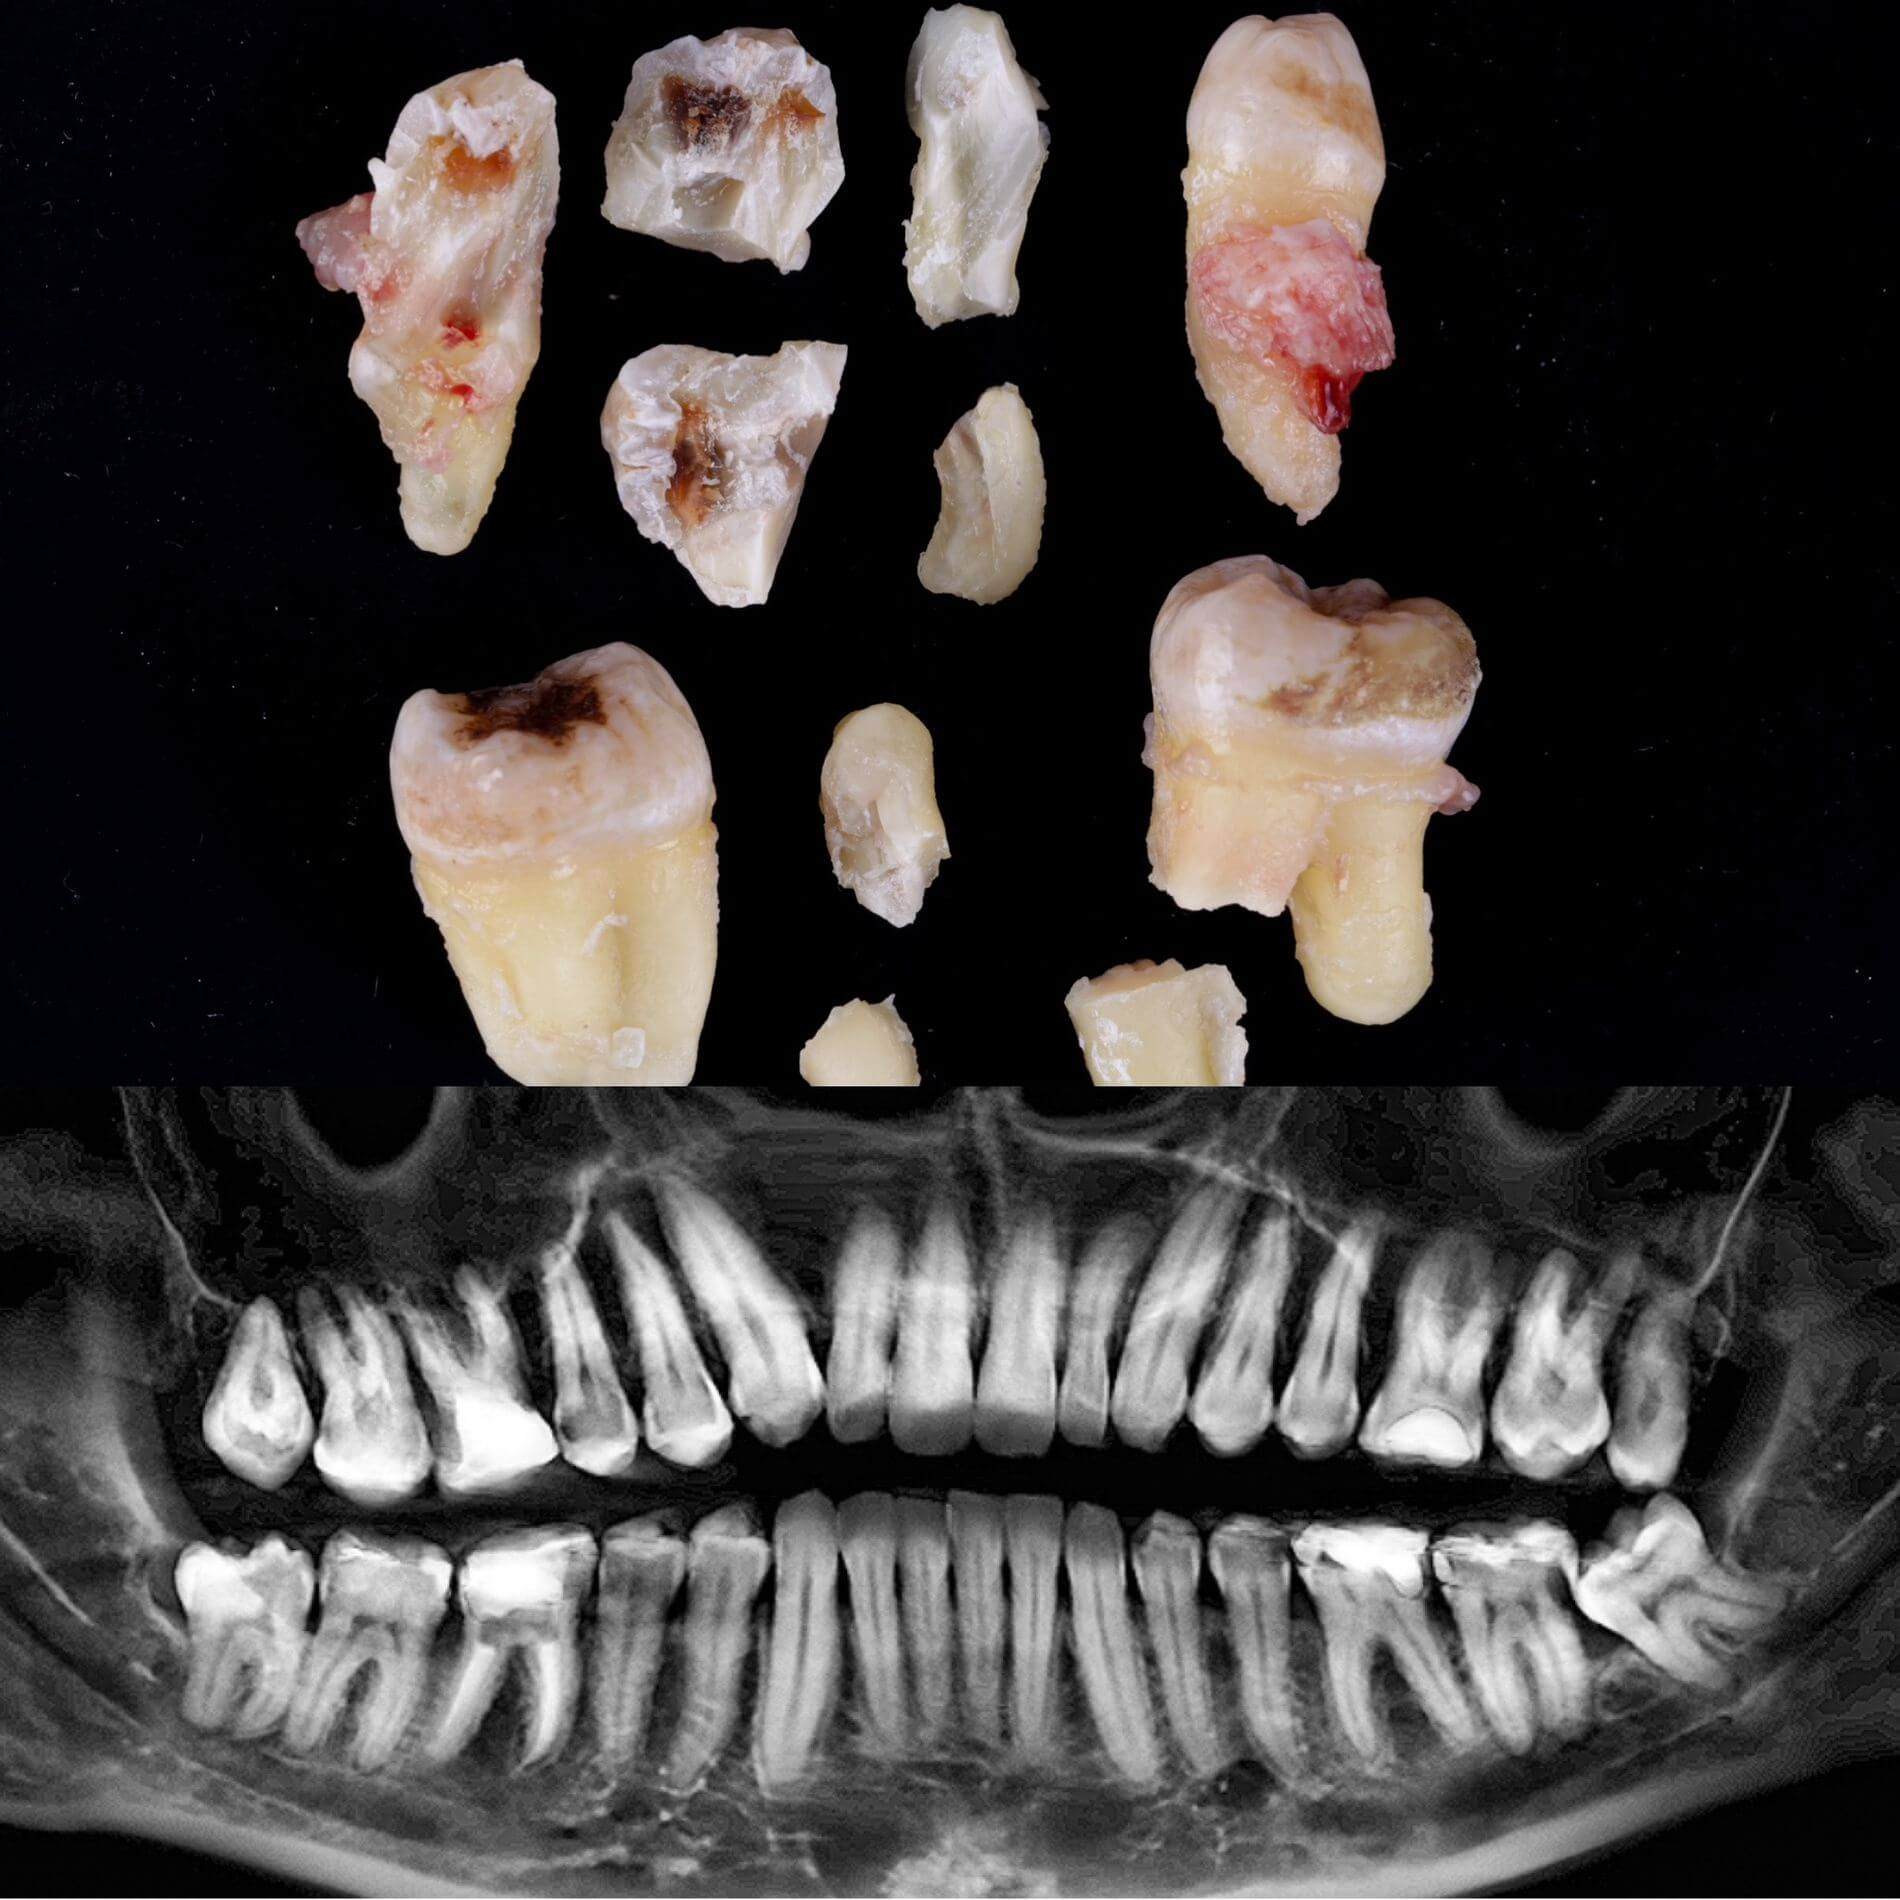

• Полное удаление зуба - если зуб полностью прорезался и имеет сросшиеся корни.

• Отдельное удаление коронки зуба и его корней - если зуб прорезан и корни растут по отдельности.

• Удаление зуба по схеме 1 или 2 с разрезом десен - если зуб прорезан частично.

• Разрез десен, освобождение зуба от близлежащей кости ультразвуком и удаление по схеме 1 или 2 - если зуб не прорезался, но беспокоит.

Галерея